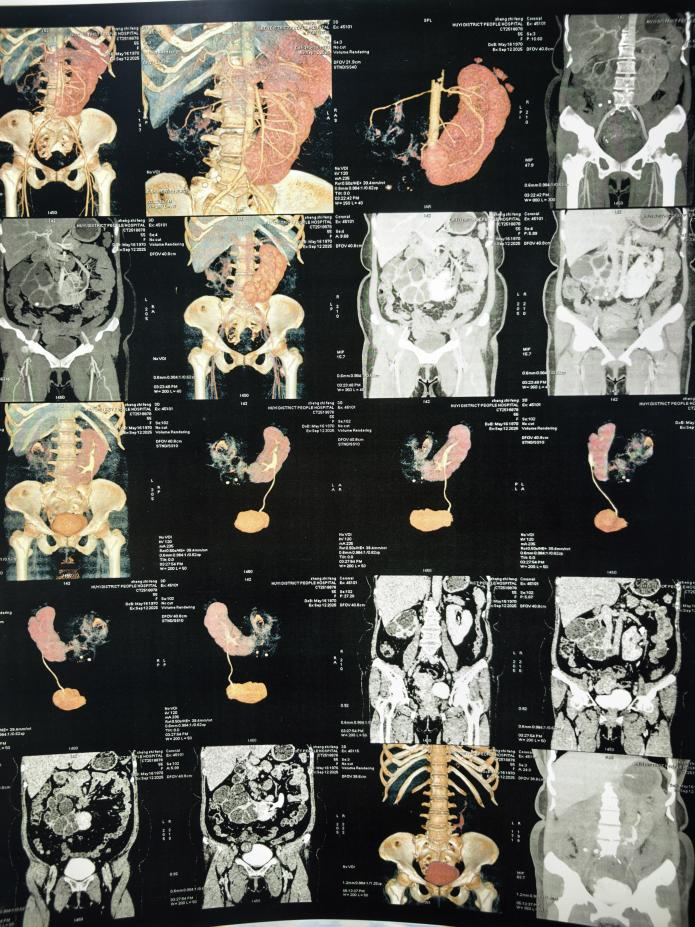

首先由泌尿肾脏病院武国军院长主刀、倪建鑫主任为第一助手,协助鄠邑区人民医院王永涛主任,完成一例马蹄肾肾盂输尿管连接部狭窄的患者行机器人辅助腹腔镜下右侧肾盂成形术。

然后由泌尿肾脏病院肾上腺高血压外科中心倪建鑫主任主刀、苏瑞平主治医师为第一助手,协助鄠邑区人民医院王永涛主任完成一例重度肾积水、无功能肾患者行机器人辅助腹腔镜下左肾切除术。